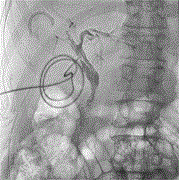

Perforation of sigmoid colon by a migrated intrauterine contraceptive device (IUCD), diagnosis and surgical management: a case report

Muhammad E A Khan and others

Journal of Surgical Case Reports, Volume 2025, Issue 1, January 2025, rjae803, https://doi.org/10.1093/jscr/rjae803